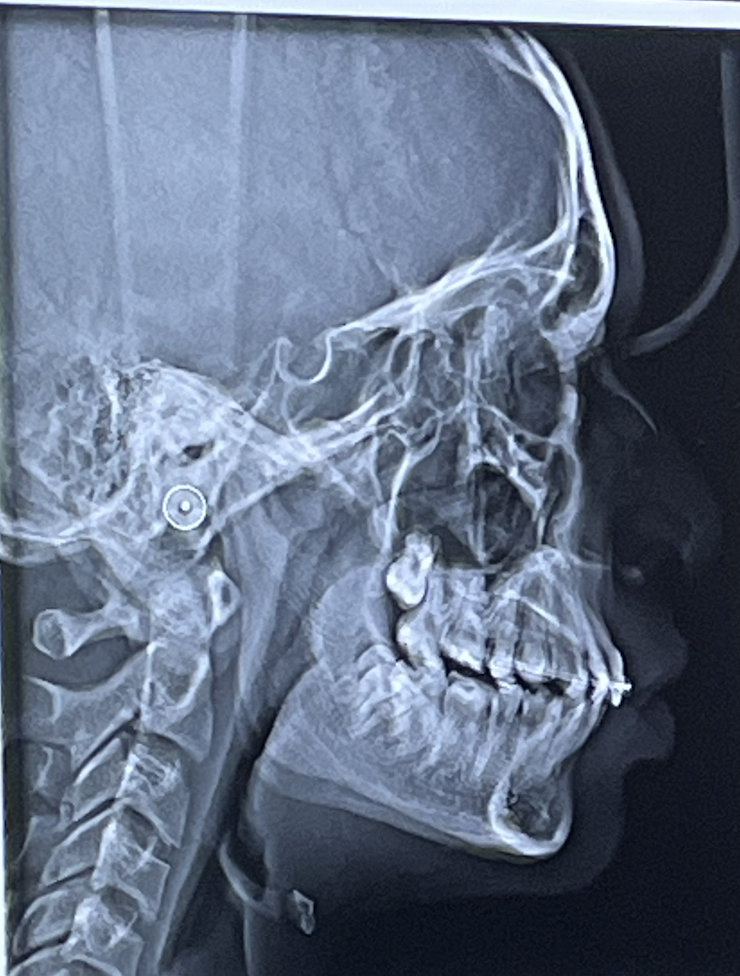

This is for showcasing the zygomatic process of the maxilla area, ri?